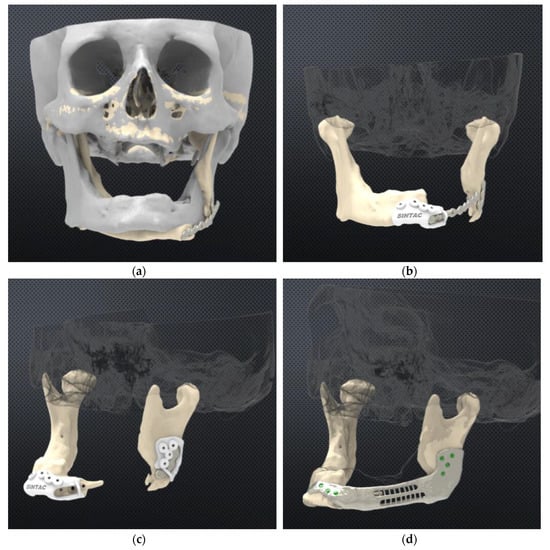

2.1. Protocol for Computer-Assisted Design and Manufacturing Bridging Plate

2.2. Surgical Procedure